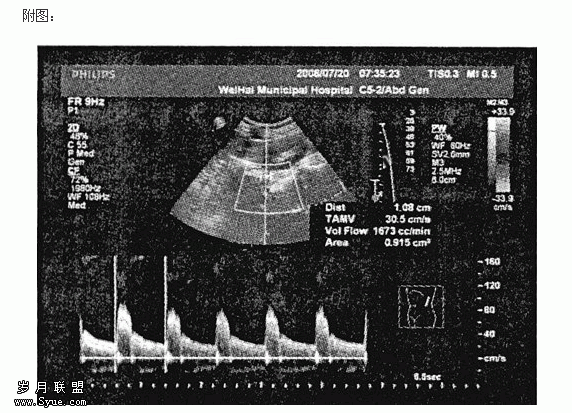

糖尿病患者的肾血流量测量(GFR161ml/min)

使用Philiph IU22彩色多普勒超声诊断仪,探头频率2.5MHz。患者均空腹状态检查。取侧卧位,首先在肾脏冠状切面测量肾脏最大长径(L)和宽径(W),随后在肾门处旋转探头,在横断面测量厚径(T),内存测量软件自动计算出肾脏体积(V),以体表面积(S)加以较正。体表面积公式采用人适用的回归方程式:S=0.0061×身高(cm)+0.0124×体重(kg)-0.0099。然后嘱受检者吸气后屏气,分别在肾窦中部的段动脉(SRA)、肾锥体两侧的叶间动脉(IRA)和皮髓质交界处的弓形动脉(ARA)内测量各段肾动脉的收缩期最大血流速度(Vsmax)、舒张末期最低血流速度(Vdmin)和阻力指数(RI)。最后,在肾门处分别找到左右主肾动脉(MRA),将图像局部放大,在彩色多普勒血流信号引导下,脉冲多普勒血流夹角<30°,当显示3~5个相同形态频谱时冻结图像,使用内存肾血流量测量工具软件,自动显示频谱包络线,在二维图像上测量主肾动脉内径,软件自动计算出肾血流量(Q),以体表面积加以较正。所有参数均取左右肾的平均值。